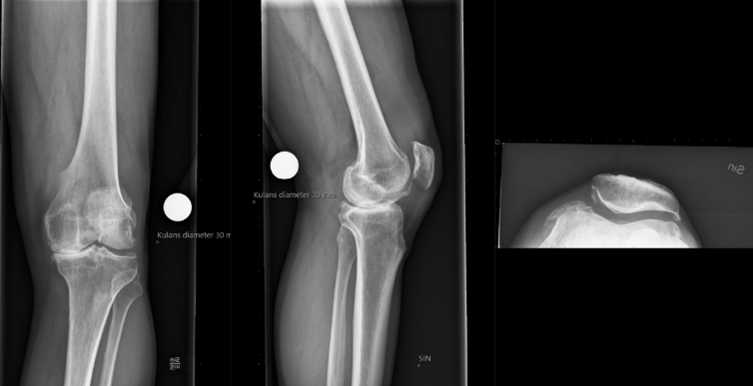

Vad ser du på bilden?

• Medial gonartros och från sidan ses oregelbundenheter i den femorala-patellära leden

• Till höger lite pålagringar och liten nabb till höger

Röntgen inför proteskirurgi knä

• Viktigt i utredning för rätt vinkel av sågning osv. Kulan på bild är 30 mm

• Figursågning för att protesen ska passa perfekt. 6 grader valgus. Tibia rätvinkligt i frontalplan. Vi vill ha o-gradigt i HKA och efter som lårbenshalsen sticker ut lite snett vill vi ha lite valgus.